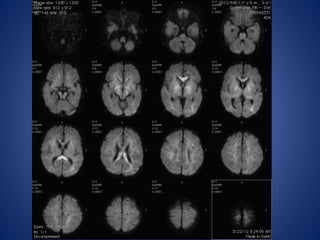

13 yrs male, with history of seizures with cilinical suspicion of febrile

encephalitis.

DWI

ADC

IR